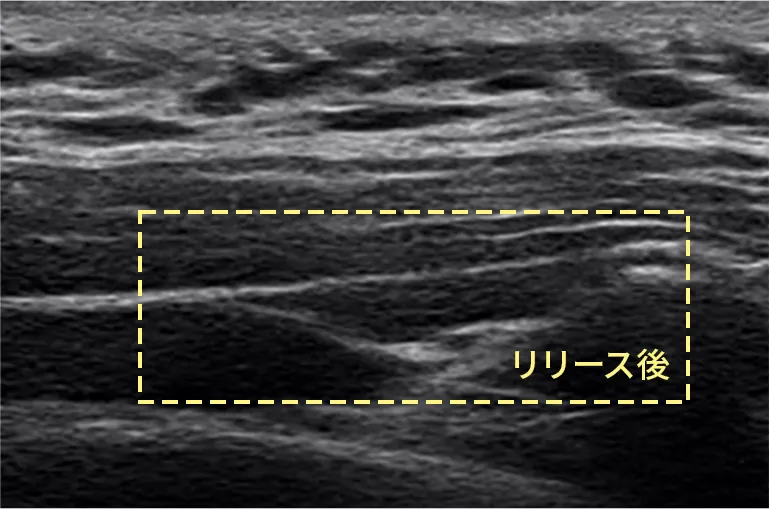

• 筋膜リリース注射前 筋膜リリース注射前のエコー写真

• 筋膜リリース注射後 筋膜リリース注射後のエコー写真